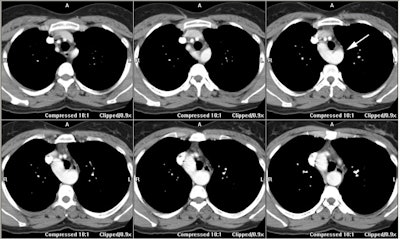

Right aortic arch with aberrant left subclavian artery:

In this patient with a right arch the left subclavian artery arises as the last branch from a large diverticulum (white arrow)